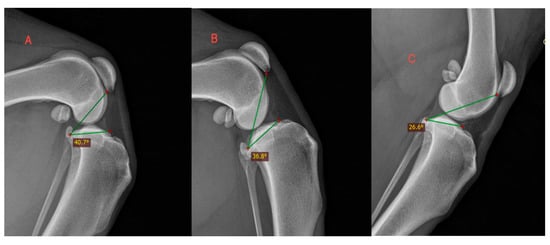

| Weight Group | Stifle Angle | Mean TPPA | ±SD 1 |

|---|---|---|---|

| ~45° | L | 43.67° | |

| M | 40.28° | ||

| S | 37.92° | ||

| Across groups 2 | 40.68° | ±4.28° | |

| ~90° | L | 35.12° | |

| M | 34.80° | ||

| S | 35.62° | ||

| Across groups | 35.26° | ±3.88° | |

| ~135° | L | 29.32° | |

| M | 26.37° | ||

| S | 28.06° | ||

| Across groups | 28.23° | ±3.54° |